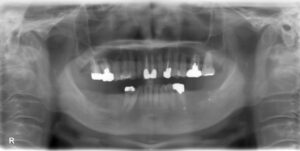

下顎臼歯4本欠損症例

BEFORE AFTER 52歳女性/下顎4本/インプラント埋込手術 【治療内容】 下顎臼歯のお痛みと腫れを主訴にご来院…